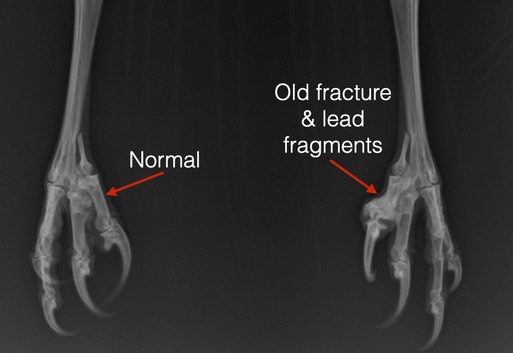

And finally, the hawk had a crooked toe on his left foot that was the result of a gunshot injury. He had been shot some months ago and recovered. Even with a horribly overgrown beak and a mostly nonfunctional left halux (the grabber toe) the hawk was in good body condition. All this before his first birthday.